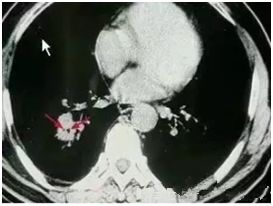

●高危結(jié)節(jié)

●結(jié)節(jié)呈毛栗子樣,周圍有角(棘突)和細(xì)小毛刺生長

●結(jié)節(jié)如月亮,周圍有一圈暈

●結(jié)節(jié)呈分葉狀

●多位于上葉結(jié)節(jié)

●結(jié)節(jié)里有較粗的血管牽扯進(jìn)來

●結(jié)節(jié)里有透亮的小空泡(空氣支氣管征)

●結(jié)節(jié)外圍有胸膜牽拉征象(臍凹征)

●隨訪3—6月以上,結(jié)節(jié)明顯增大或內(nèi)部密度增高

對于以上的高危結(jié)節(jié)應(yīng)由胸外科、腫瘤內(nèi)科、呼吸科和影像醫(yī)學(xué)科醫(yī)生集體會(huì)診,決定是否需要進(jìn)一步檢查(包括支氣管鏡、CT增強(qiáng)掃描、經(jīng)皮穿刺活檢等)明確診斷,以及采取什么方法治療。

對高度懷疑為惡性者且適合于外科手術(shù)者,首選手術(shù)治療。對肺癌可能性小的病例可抗炎治療7—10天,休息一周后復(fù)查,結(jié)節(jié)增大或無變化,可進(jìn)入臨床治療,結(jié)節(jié)縮小可動(dòng)態(tài)隨訪。